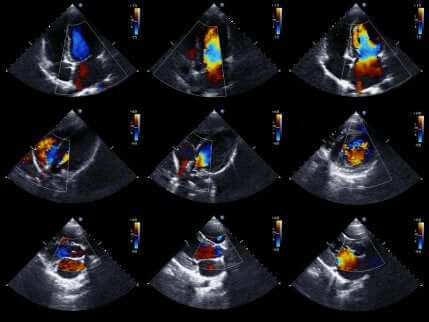

Ηχοκαρδιογράφημα

Τέλος, τα ηχοκαρδιογραφήματα ή υπερηχογραφήματα καρδιάς, επιτρέπουν στους γιατρούς να μελετήσουν με μεγαλύτερη λεπτομέρεια την καρδιά.

Το ηχοκαρδιογράφημα είναι μια πολύ δημοφιλής εξέταση. Ο λόγος είναι πως λαμβάνει εικόνες από την καρδιά. Έτσι, μπορούν να εκτιμήσουν την κατάσταση των θαλάμων της καρδιάς και τις κινήσεις τους προκειμένου να επιβεβαιώσουν ή να αποκλείσουν την ισχαιμία.

Επιπροσθέτως, αξιολογείται το μέγεθος και η δύναμη της καρδιάς, καθώς και η κατάσταση των τοιχωμάτων των καρδιακών θαλάμων. Γενικά, πρόκειται για μη επεμβατική εξέταση χωρίς να υπάρχει κίνδυνος για την υγεία του/ης ασθενούς. Ο λόγος πίσω από αυτό είναι η χρήση υπέρηχων για την απόκτηση εικόνων από την καρδιά.

Αν ο/η γιατρός χρησιμοποιήσει αυτή την εξέταση, η απουσία ενοχλήσεων στα τοιχώματα της καρδιάς κατά την κίνησή της, αποκλείει και την ύπαρξη ισχαιμίας. Εξάλλου, οι ενοχλήσεις στην κίνηση της καρδιάς δεν υπάρχουν αποκλειστικά στο οξύ στεφανιαίο σύνδρομο. Γι’ αυτόν τον λόγο, τα αποτελέσματα των εξετάσεων και τα συμπτώματα θα πρέπει να αξιολογηθούν μαζί.